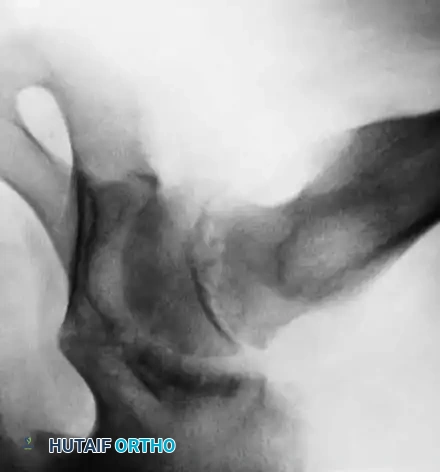

Slipped Capital Femoral Epiphysis (SCFE) represents a unique and complex pediatric hip disorder. While technically a type I transepiphyseal fracture-separation, SCFE is distinguished from standard epiphyseal separations by its distinct natural history, insidious pathogenesis, and biomechanical etiology. The disorder is characterized by the displacement of the proximal femoral epiphysis posteriorly and inferiorly relative to the femoral neck.

The pathogenesis of SCFE is multifactorial, involving a combination of mechanical shear forces and underlying endocrine or metabolic susceptibilities. During the adolescent growth spurt, the physis widens and weakens, making it vulnerable to the increased mechanical loads associated with obesity or rapid growth. Kordelle et al., utilizing three-dimensional computed tomography (CT) analysis in 30 slips, identified significant morphological variations predisposing to SCFE. They noted a reduced femoral anteversion averaging 7 degrees (compared to a normal 12.7 degrees) and a reduced femoral shaft angle of 134.2 degrees (compared to a normal 141 degrees). Furthermore, their analysis confirmed an absence of acetabular remodeling following the slip, underscoring the permanent biomechanical alteration of the joint if left untreated.

* Acute Slips: Sudden onset of severe symptoms present for less than 2 weeks. Radiographs reveal epiphyseal displacement with absolutely no evidence of bone healing or remodeling.

* Chronic Slips: Gradual onset of symptoms lasting longer than 2 weeks. Radiographs demonstrate bony healing and remodeling along the posterior and medial femoral neck.

* Acute-on-Chronic Slips: Symptoms lasting longer than 1 month, punctuated by a recent, sudden exacerbation of pain following a relatively trivial injury.